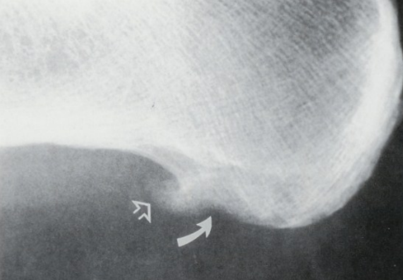

What disease is this? What does the arrow show? | Non-articular psoriatic arthritis Arrow = 'fluffy spur' |